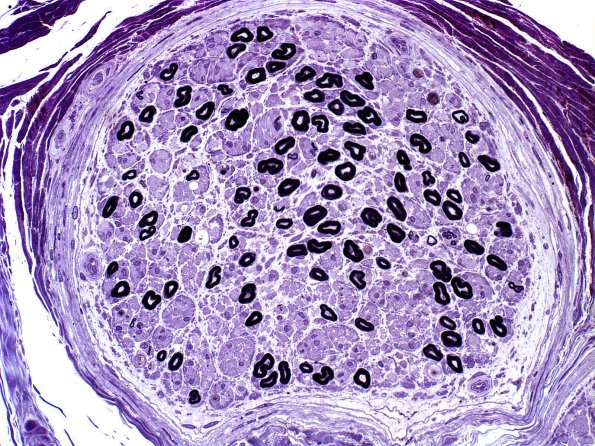

Washington University Experience | PERIPHERAL NEUROPATHY | 4 AXONAL DEGENERATION | 2 Plastic Sections | 24A1 Axon loss, mostly small MF (Case 24) Plastic 1

24A1,2 The sural nerve of this patient with amyloidosis shows preferential loss of small myelinated axons.